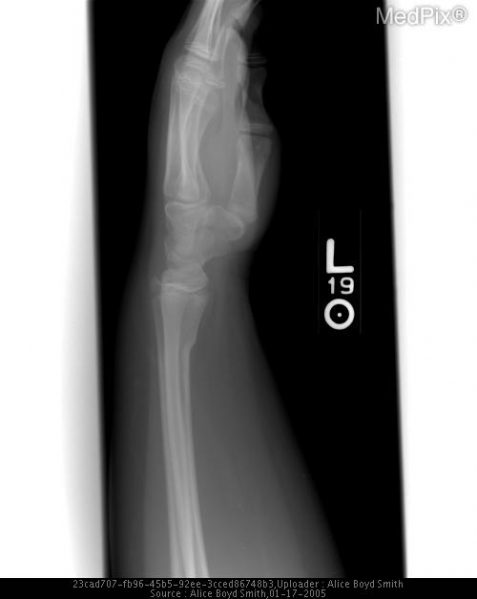

Distal Radius Torus Fracture/Buckle Fracture Smith ABS - MedPix Images Open-I

| actual | 01:16 14 ago 2019 | 500 × 628 (118 kB) | Rossdonaldson1 (discusión | contribs.) | Distal Radius Torus Fracture/Buckle Fracture Smith ABS - MedPix Images Open-I |